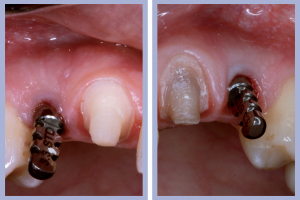

- Figg. 15a, b – Inserimento e preparazione del moncone temporaneo di destra

- Figg. 16a, b – Consegna della corona provvisoria in resina di destra

- Figg. 17a, b – Inserimento e preparazione del moncone temporaneo di sinistra

- Fig. 18 – Consegna della corona provvisoria in resina di sinistra

- Fig. 19 – Visione d’insieme al termine dell’intervento

- Figg. 20a, b, c – Controllo clinico e radiologico a 2 settimane dall’intervento

– Posizionamento e preparazione dei monconi temporanei (Figg. 15-20);

– Adattamento e consegna delle corone provvisorie (Figg. 15-20).

Il posizionamento implantare è stato seguito dal posizionamento e dalla preparazione intra-orale dei monconi temporanei e dalla successiva consegna, previa ribasatura, delle corone provvisorie. Durante la fase di attesa dell’osteointegrazione degli impianti si procedeva alla preparazione protesica dei canini (nella posizione dei laterali) per ottenere, tramite ricopertura protesica, la forma degli incisivi laterali.